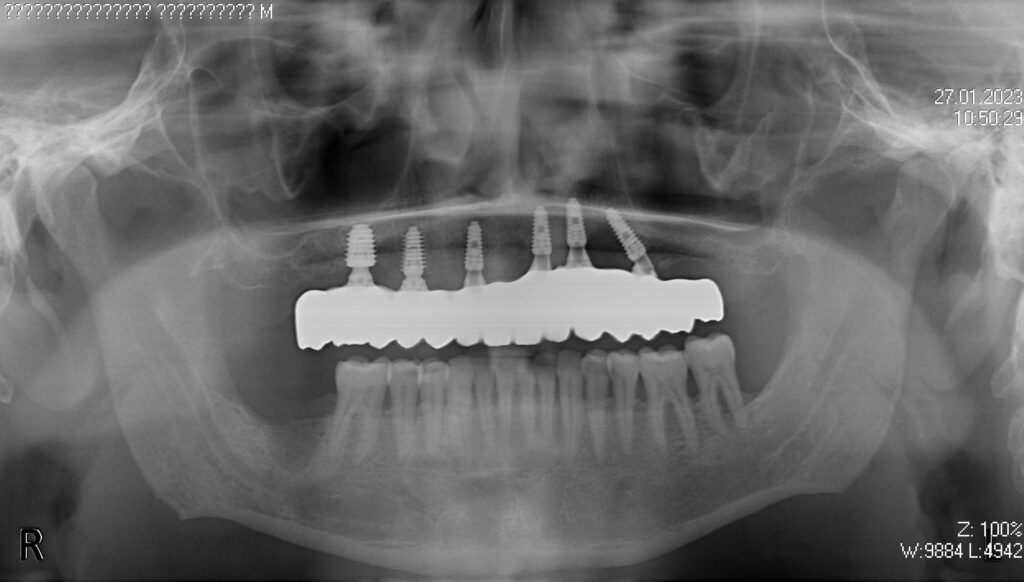

Пациент продолжает лечение спустя 3 месяца после имплантации и установки временного металлоакрилового протеза с опорой на 6-ти дентальных имплантантах Megagen Anyone.

снимок

работы врача